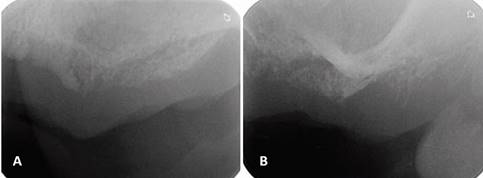

Periapical radiographs were initially ordered. They showed a loss of continuity of the bony trabeculae with irregular, faint osteolytic areas without root debris or foreign bodies (Fig.4 A, B). A CBCT of the maxilla was ordered to evaluate the extent of the lesion. The CBCT showed a radiolucent and osteolytic area at the maxillary bone tissue, measuring 8.5 mm x 5.4 mm, with irregular, poorly defined borders, and which did not involve the buccal, palatine, or maxillary sinus cortical areas (Fig. 5). Microscopic study of the necrotic tissue debris confirmed areas of bone tissue necrosis with inflammatory infiltrate, confirming the MRONJ diagnosis.

(A) Loss of bone density with a poorly defined radiolucent area. (B) Loss of bone trabeculation and of continuity of the bone ridge, with irregular radiolucent and radiopaque areas.